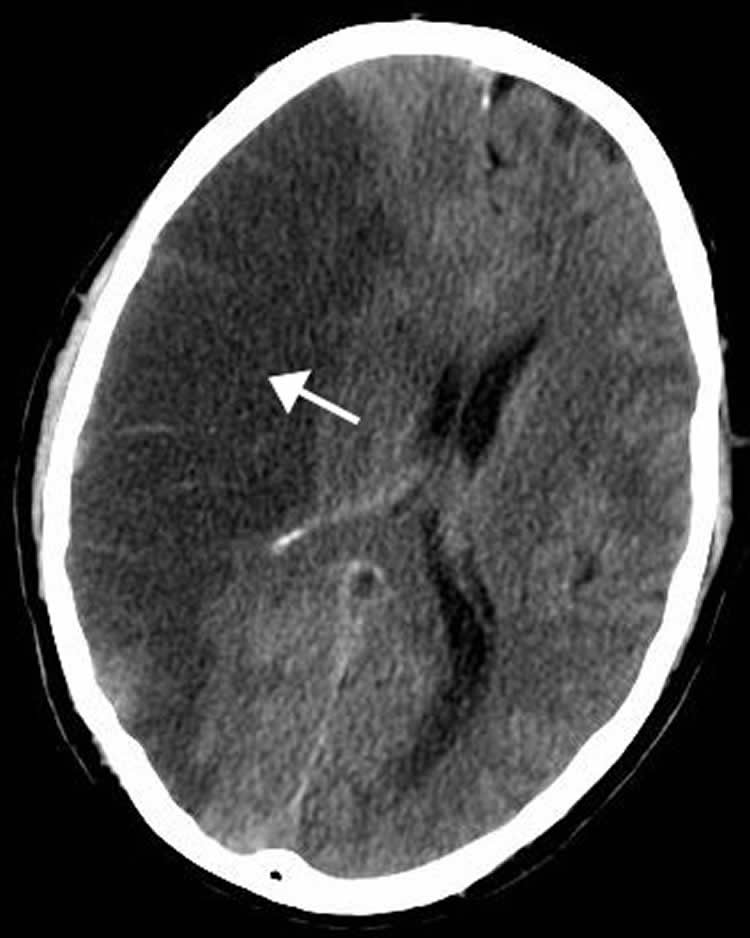

In the study, researchers reviewed a Kaiser Permanente database of 2.5 million children and identified 102 children who had an ischemic stroke – a stroke that occurs as a result of an obstruction within a blood vessel supplying blood to the brain – without a major infection such as meningitis or sepsis. The researchers then compared them with 306 children without stroke. Medical records for the group of children who had a stroke were reviewed for minor infections up to two years before their strokes.

Image Source: The image is credited to Lucien Monfils and is licensed Creative Commons Attribution-ShareAlike 3.0 Unported